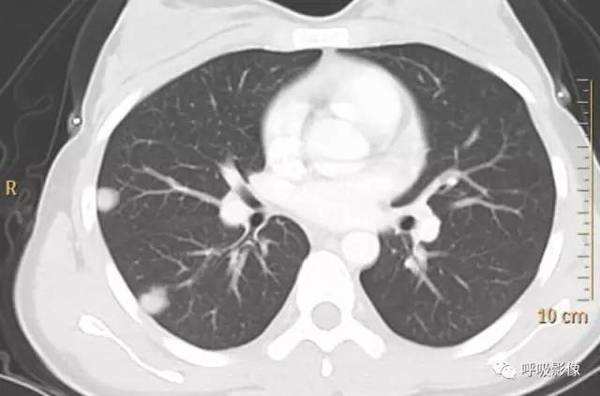

随着β-HCG水平的变化 ,最终发展为边缘较为光滑、密度均一的结节或肿块影(图3),可有空洞(图4),肺门或纵隔淋巴结常无肿大。

图3 女,22岁 绒癌肺转移。表现为典型结节。

图4 女,26岁 绒癌肺转移。表现为结节、空洞,晕征可见。